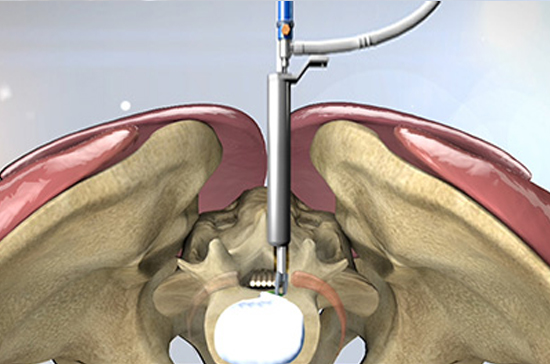

양방향 척추내시경 신경감압술

양방향 척추내시경 신경감압술은 약 4㎜ 가량 작은 구멍을 두군데 뚫어 내시경을 삽입해 협착된 부위를 제거하는 수술법입니다.

한쪽은 내시경을 삽입해 정확한 원인을 찾는 동시에, 다른 한쪽으로는 수술기구를 삽입해 척추관협착증의 주된 원인인 인대와 관절의 골극을 제거하는 첨단 수술 기법입니다.